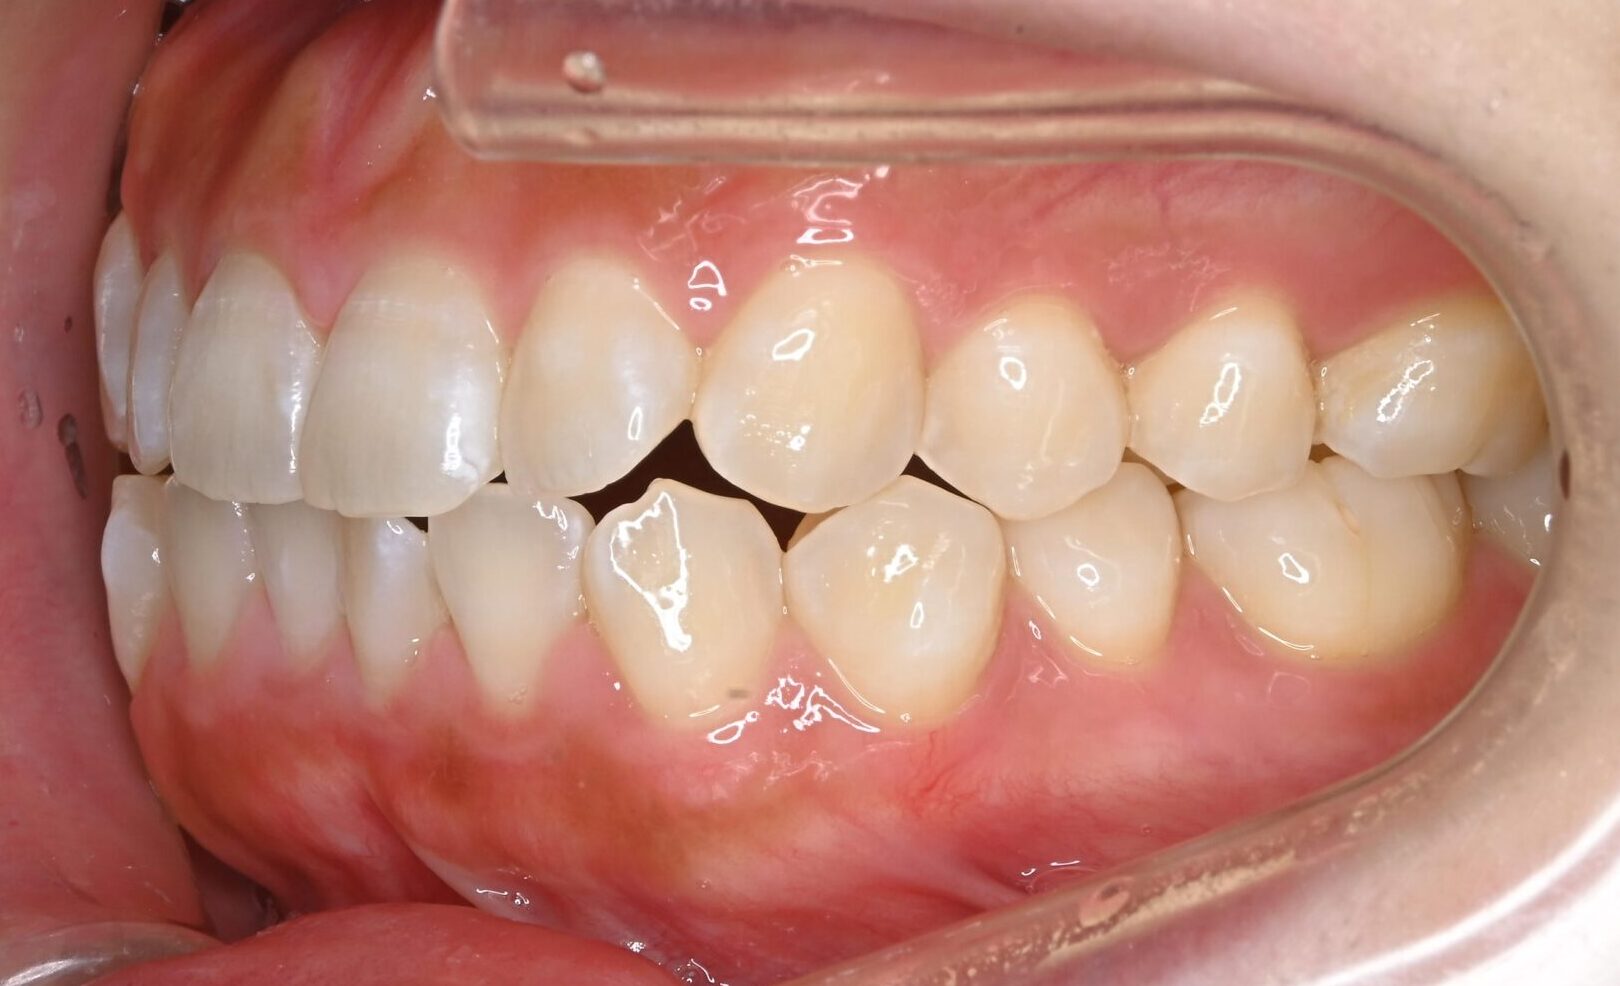

症例写真 before